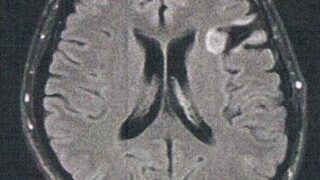

GLIOMA:手術後132ヶ月目の検査

手術から11年が経過した。半年ごとの定期検査です。検査概要びまん性星細胞腫グレード2(悪性転化しやすい腫瘍)MRI検査: 造影剤なし / 造影剤あり造影剤ありの場合:4時間前から絶食し、MRIの1時間前に血液検査を済ませる。診断結果着実に大...